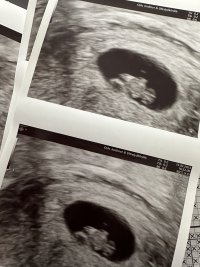

Ble målt til 12+6.

7+4 vs 9+1. Selv om de 11 dagene kjentes ut som 2 mnd! 9+1 og spretter litt rundt inni der

Klarte ikke å vente en hel uke til, men ble så letta og glad